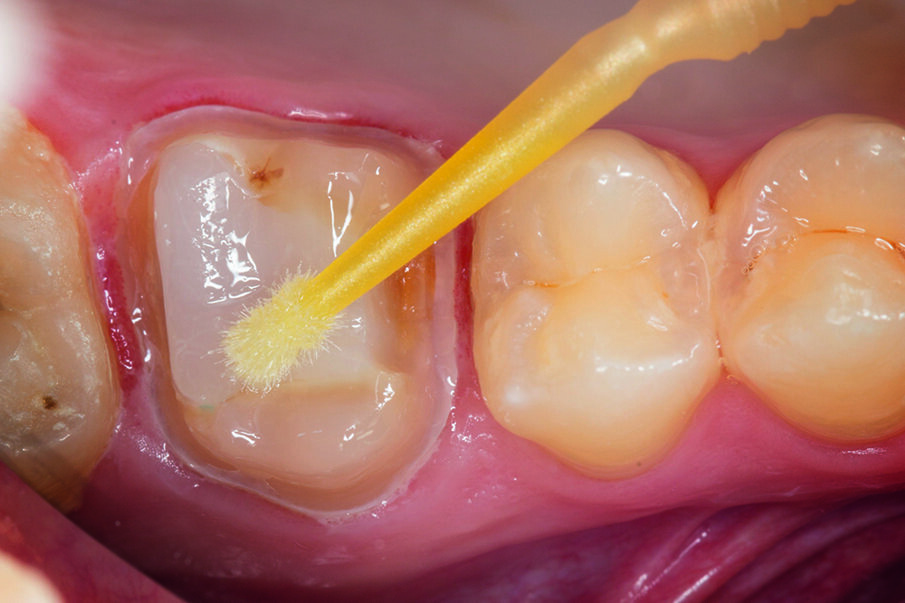

Fig. 3: Application of the etch&rinse adhesive Prime&Bond Universal™